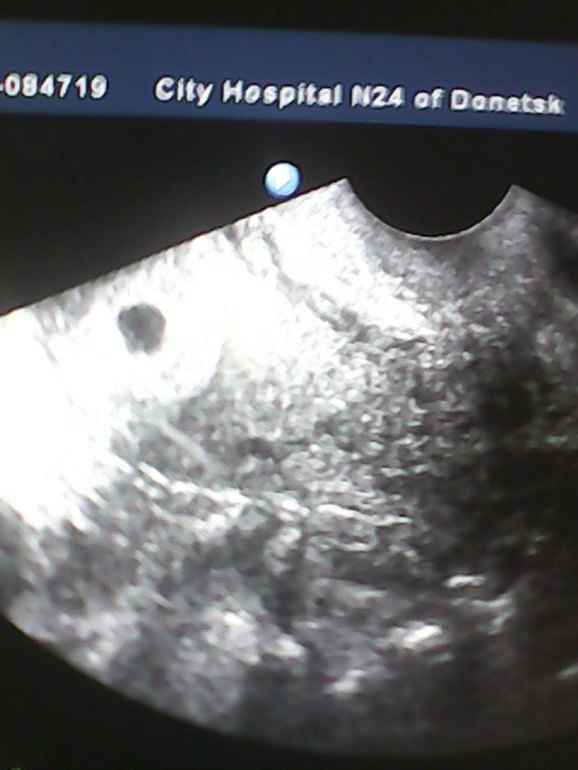

Ура мои полосочки были не обманом .На сегодня у меня уже 4 недельки,очень переживаю ,сроки маленькие ,что б росс хорошо))))Тошнит до ужаса и грудь болит ,уже лифчик себе купила ,так как без него не выносимо ходить.Наконец то я дождалась полосочек.Хочу сказать девочки не сдавайтесь .Я через многое прошла в своем возрасте ,и руки нам опускать нельзя .Я справилась с поликистозом ,и теперь держу кулачки с мужем что б с нашим малышом было все хорошо .Вот пока плодное яйцто в матке видно было на двух недельках